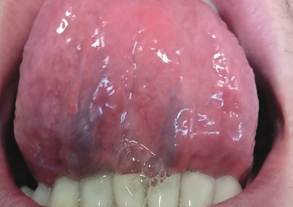

En la zona motivo de consulta, se aprecia en cara ventral de lengua dos placas blanquecinas, una de mayor magnitud en parte media de lengua, y otra de menor extensión en la mitad izquierda de la misma, ambas indoloras (figura 2). Se pregunta al paciente si presenta al momento alguna otra lesión en el cuerpo, lo cual niega. El diagnóstico presuntivo fue de sífilis secundaria, por lo que se solicitó crasis sanguínea y estudios serológicos complementarios de diagnóstico: reacción plasmática rápida (RPR) mide los anticuerpos (AC) liberados por las células huésped dañadas así como también por los treponemas. Dichos AC no sólo se producen como consecuencia de la sífilis sino también en respuesta a enfermedades no treponémicas de naturaleza aguda y crónica donde hay daño tisular. Por dicho motivo se realiza una segunda prueba más específica para detectar AC contra el treponema que causa la sífilis una de ellas es AC anti Treponema pallidum. utilizando el método de la quimioluminiscencia. También hepatitis B, C y VIH a fin de ampliar el protocolo de infecciones de transmisión sexual. El RPR arrojó un valor de 1024 unidades siendo el resultado óptimo: 0–0,001 y la quimioluminiscencia de 28.10 considerando que a partir de 1.0 ya es positiva, mientras que las demás pruebas serológicas resultaron no reactivas (figura 3).

Figura 2. Lesión en cara ventral de lengua.

Confirmado el diagnóstico de sífilis secundaria, se realizó la correspondiente derivación del paciente al centro de salud para recibir el tratamiento adecuado, donde fue medicado con tres dosis de penicilina G benzatínica 2.400.000 UI intramuscular. Post tratamiento se controló al paciente observando una notable mejoría de la lesión, evolucionando a la remisión de la misma (figuras 4A y 4B).

Figura 4B. Control luego de iniciado el tratamiento observándose una reducción de la lesión.